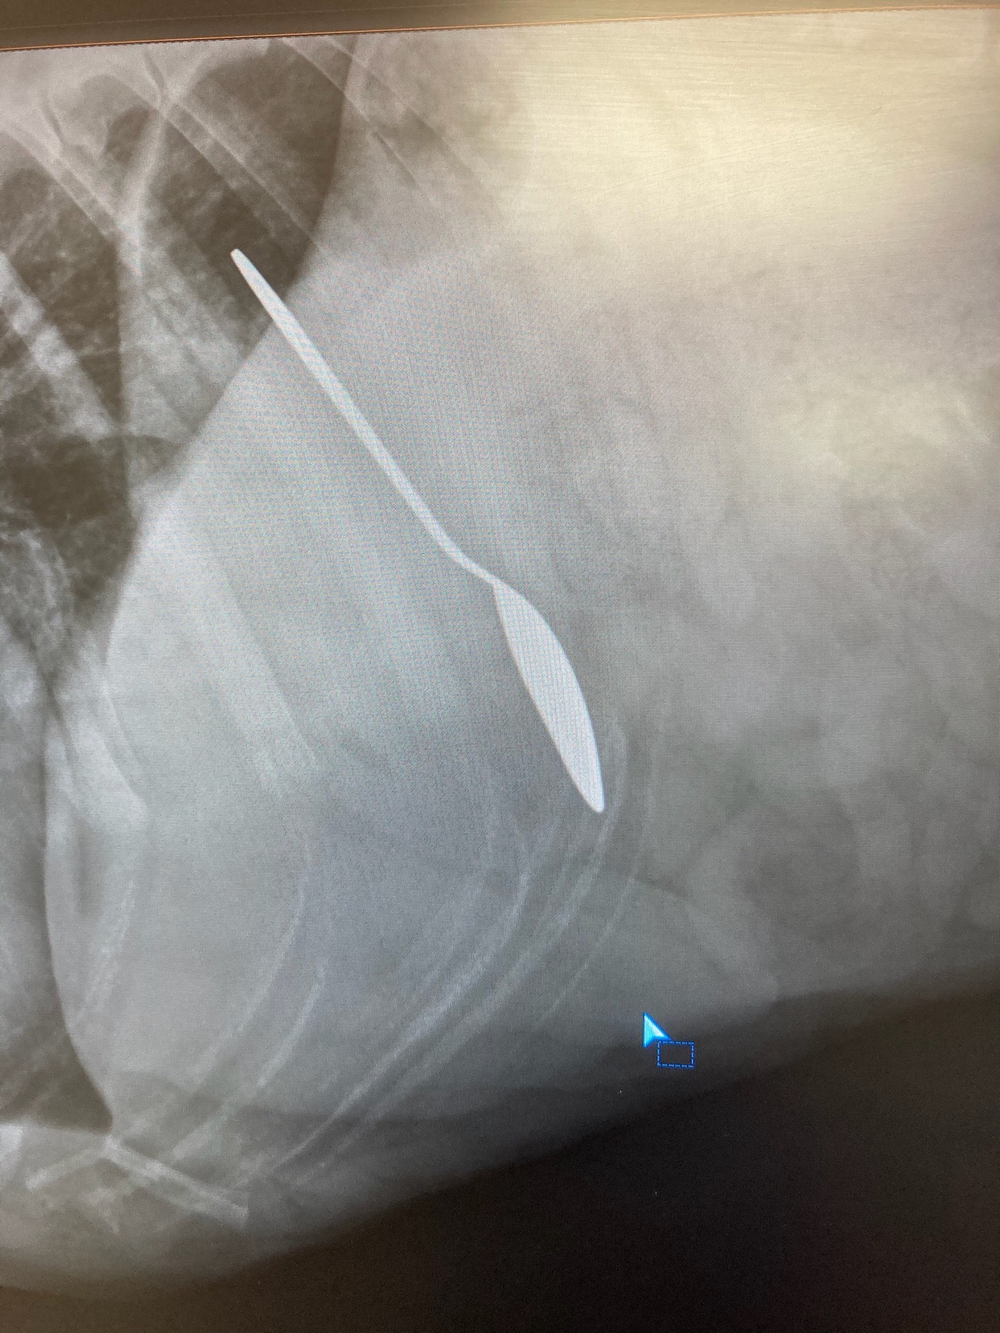

La radiographie vétérinaire est une technique d’imagerie médicale qui permet de visualiser les os, les organes internes, les tissus mous et toutes les structures internes du corps des animaux. Les radiographies vétérinaires sont couramment utilisées pour diagnostiquer des fractures, des maladies pulmonaires, des problèmes cardiaques, des obstructions intestinales, des tumeurs, et bien d’autres affections.

C’est un outil précieux pour notre équipe vétérinaire afin d’établir un diagnostic précis, et planifier un traitement adapté pour vos chiens, chats et Nacs.